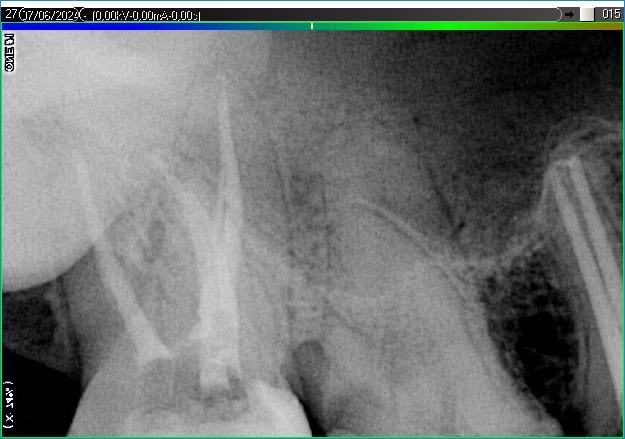

Вилучення інструменту з каналів зуба